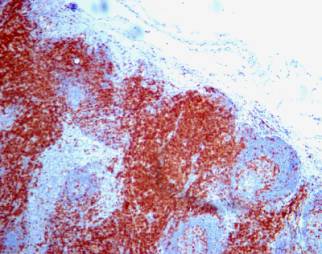

Na řezu mízní uzlinou jsou červeně zbarveny bílé krvinky nesoucí na svém povrchu molekulu CD3. právě proti ní jsou cíleny protilátky, které pomáhají diabetikům ukonejšit jejich „rozvzteklený“ imunitní systém.